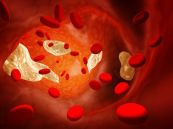

Tăng lipid máu là một thuật ngữ y khoa dùng để chỉ tình trạng nồng độ chất béo (lipid) trong máu cao bất thường. Hai loại lipid chính được tìm thấy trong máu là triglycerid và cholesterol. Tăng lipid máu còn được gọi là nồng độ cholesterol cao. Mặc dù tình trạng này có khả năng di truyền nhưng nó thường là kết quả từ những lựa chọn không lành mạnh trong lối sống. Để biết rõ hơn về bệnh lý này, mời các bạn tham khảo bài viết dưới đây.

Tăng cholesterol máu thuần túy hoặc tăng cholesterol máu gia đình là tình trạng có mức cholesterol cao do một bất thường di truyền. Mặc dù các triệu chứng hiếm khi xảy ra, một số người tăng cholesterol máu thuần túy có thể gặp: đau ngực, u cục nhỏ trên da, u vàng, tích tụ cholesterol nhỏ. Để biết rõ hơn về bệnh lý này, mời các bạn tham khảo bài viết dưới đây.